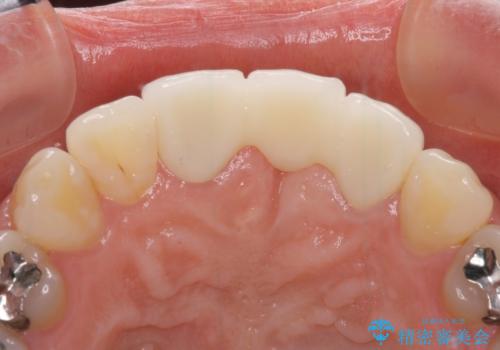

- 接着タイプの前歯のブリッジが不自然であるとのことで来院された患者様です。

欠損部の歯肉が窪んでいるため、歯肉移植により形態を改善し、オールセラミックブリッジにて補綴することとしました。

事前に装着されていた接着タイプのブリッジは、歯の切削量が少ない反面、接着界面から虫歯が進行しやすく、脱落リスクが高くなるというデメリットがあります。